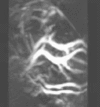

In order to capture sufficient thermoacoustic data to form an accurate 3D map of electromagnetic absorption, it is necessary to surround the anatomy being imaged with a 2D array of transducers. The world's first 3D thermoacoustic animal scanner (Fig. 8: left panel) accomplished this by combining a cylindrical array of 128 transducers (Fig. 8: center panel) with rotation of the animal being imaged about the vertical axis. The net result was to capture thermoacoustic data over the surface of a sphere surrounding the animal being imaged (Fig. 8: right panel).[11] This device was capable of visualizing structures as small as 1/3 millimeter. An animated 3D image of the vasculature in the head of a mouse is displayed in Fig. 9. This animated image was acquired using near infrared radiation at 800 nm, where optical absorption by blood is higher than surrounding tissues. Therefore, the vasculature is preferentially visualized.